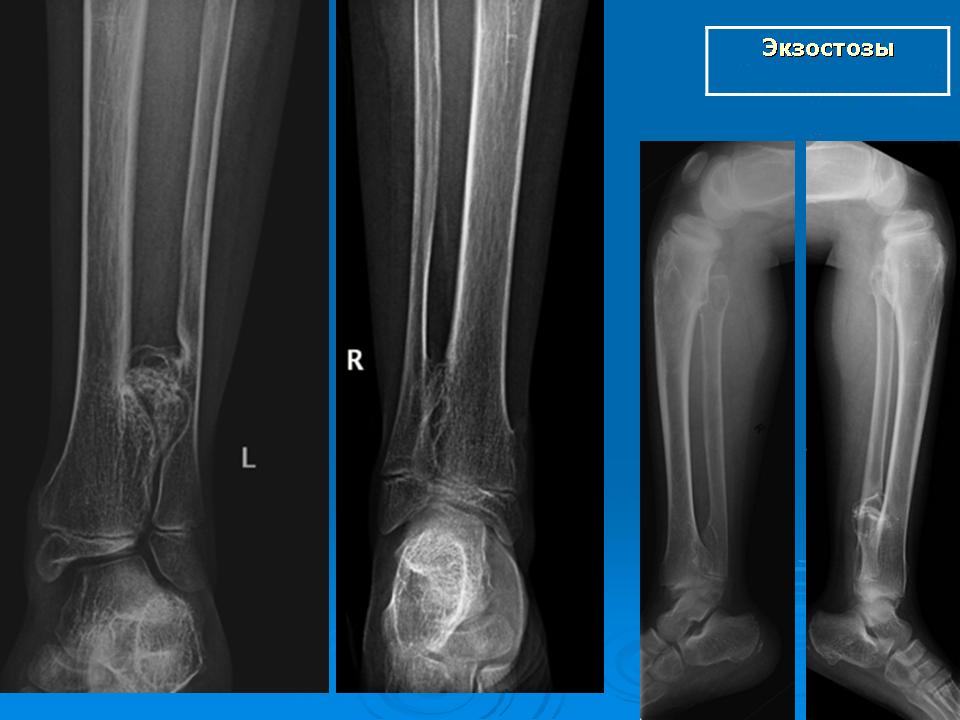

Основным методом обследования при экзостозе является рентгенограмма. На снимке можно увидеть аномальные изменения в костной структуре. Специалист обращает внимание на уменьшение высоты кости, фрагментацию пораженных отделов кости, а также беспорядочное чередование темных и светлых участков. Определить диаметр дефекта рентгеновский снимок неспособен, так как не обнаруживает хрящевую ткань.

Поскольку новообразование разрастается за счет наружного хрящевого слоя, его внутренняя структура постепенно минерализуется и приобретает характеристики костной ткани. На рентгеновских снимках экзостоза у ребенкачетко видны очертания окостеневшего тела нароста, слившегося с телом кости. При этом хрящевой слой не оставляет тени на рентгенограмме, как и обычный хрящ.